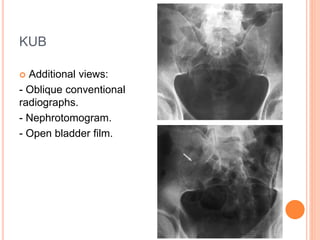

KUB

 Additional views:

- Oblique conventional

radiographs.

- Nephrotomogram.

- Open bladder film.